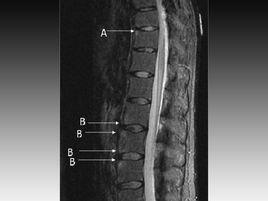

(6)X線、CT和MRI檢查可顯示骶髂關節炎(16%~30%)和脊柱炎(約20%)。

(4)放射學

脊柱徵象:韌帶骨贅,椎體方形變,桶狀椎體,Romanus或Andersson病灶,累及骨突關節或肋骨椎骨橫突關節 1分。